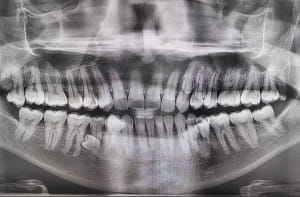

Тоді нарахували 38 зубів, що вже було значно більше за норму. Проте справжня сенсація чекала на Пратаба в кабінеті стоматолога. Рентгенівське обстеження показало, що в щелепі приховані ще чотири зуби, які на той момент ще не прорізалися. Остаточний вердикт лікарі оголосили на початку 2023 року: загальна кількість зубів становить 42.